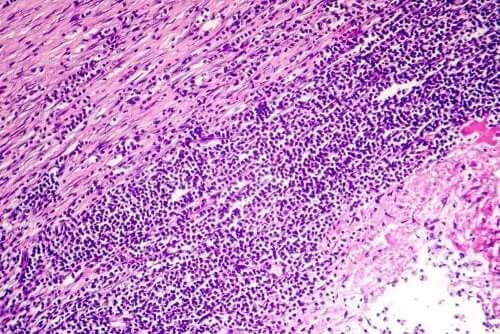

- 急性心筋炎:6週間以下の短期間で突然発症します。相対頻度として心外膜液に繋がるでしょう。症状は心臓発作とよく似ています。再発する患者の割合は少ないでしょう。

- 慢性心筋炎:心膜が厚みを帯びる、または液体が蓄積された結果として慢性の心筋炎が起こります。6週間以上続き、右心不全へと繋がることがあります。これは腹部、脛骨、足首の浮腫になります。慢性心筋炎は、線維性組織が心臓の周りに形成されたときに起き、血液を運ぶ静脈に圧力を与えてしまいます。したがって、心膜液はよどみ、体の他の部分に蓄積されてしまいます。